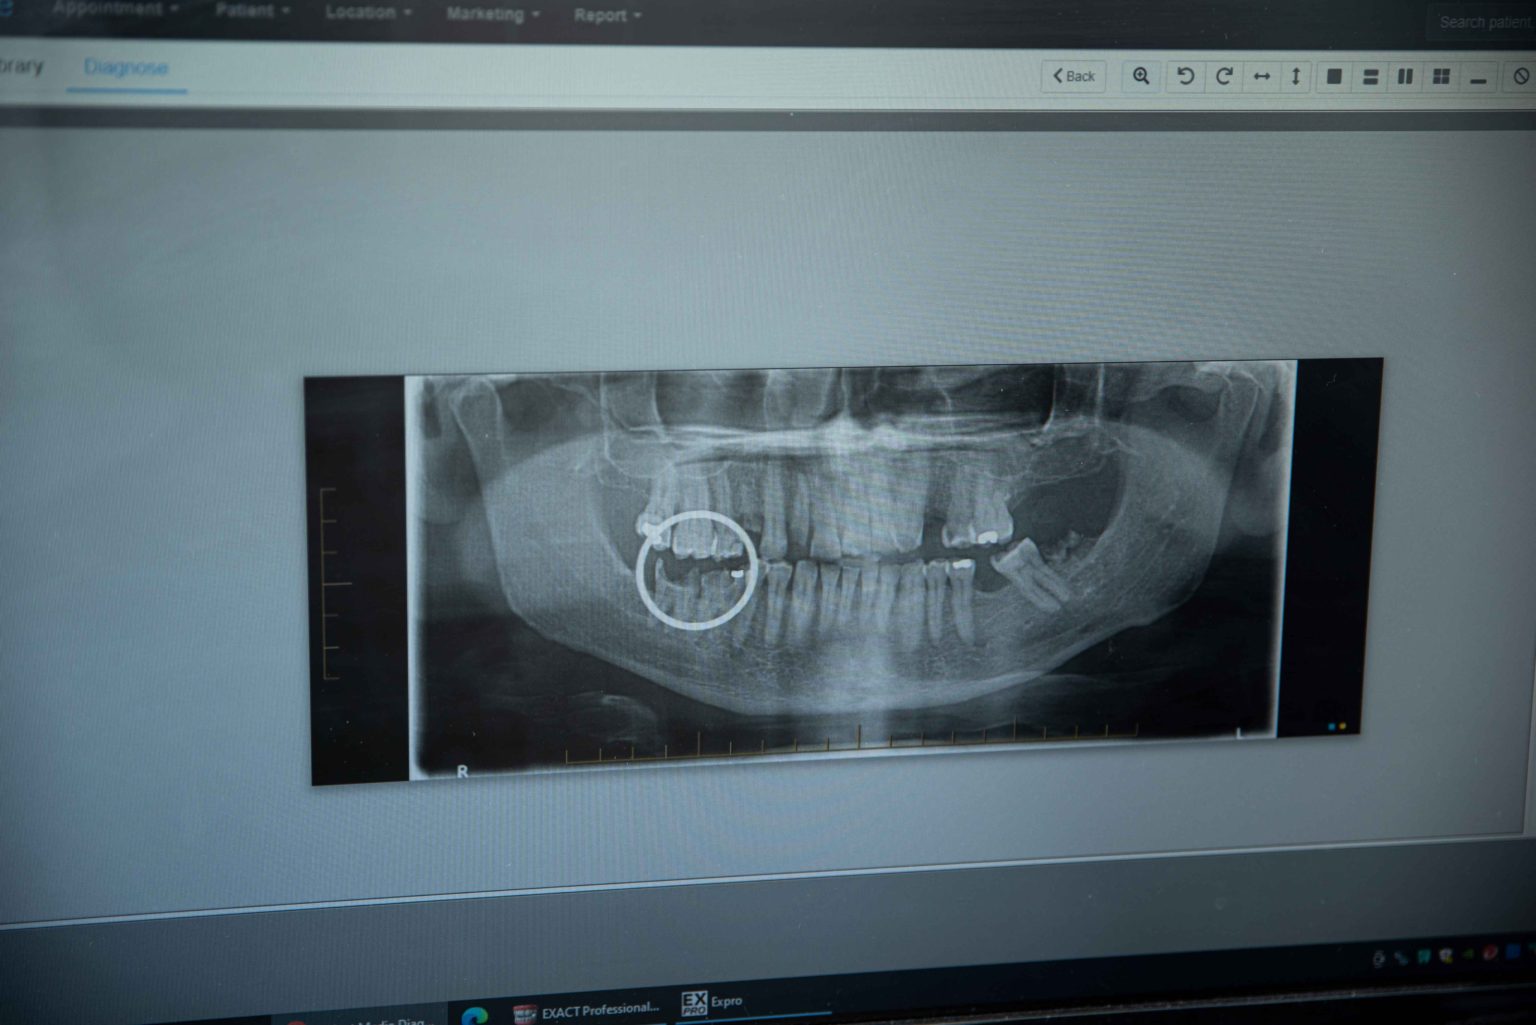

Broken Teeth

Most people aren’t aware they do it, but our team at Mount Barker Dentists can identify this habit during a regular appointment. Grinding your teeth is a common issue that, if left unchecked, can lead to broken or damaged teeth, especially if you haven’t regularly been to the dentist.

Is a cracked tooth a dental emergency?

A chipped, broken, or cracked tooth can indeed constitute a dental emergency, particularly if the tooth is broken below the gum line or if there is an issue with the gum tissue covering a broken tooth.

In such cases, emergency dental treatment is often necessary to address the broken tooth, remove any infection, and prevent further complications. Timely intervention is crucial to ensure the best possible outcome and relieve any pain or discomfort associated with the dental issue.

While it’s possible to continue living with a broken or chipped tooth, external damage may indicate potential internal damage to the tooth. If left untreated, bacteria can accumulate within the crack, potentially leading to pain, infection, and even an abscess.